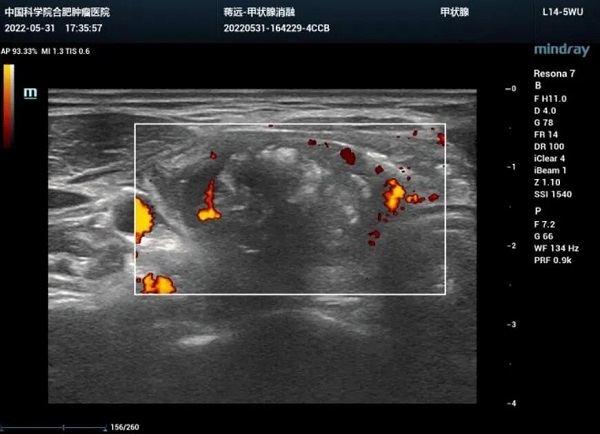

该患者系一位青年女性,患甲状腺巨大结节多年,影响美观,吞咽困难。经反复评估,该患者结节虽然大,但位置好,可以进行消融手术。与患者沟通后,在局麻下,对该结节进行了微波消融术。手术半小时结束,将原本血流丰富的结节彻底消灭。

消融手术全程超声实时引导,视野清晰,安全可靠